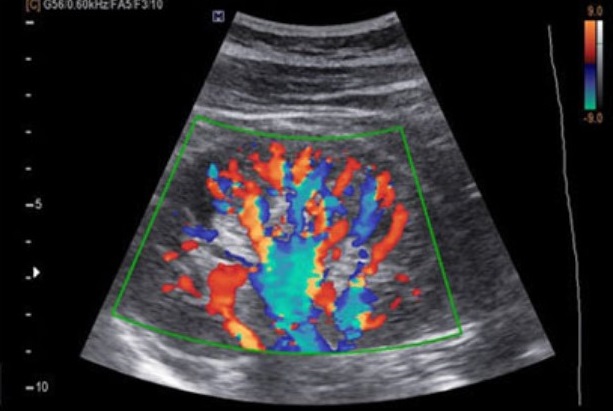

Color Doppler

در داپلر رنگی، اطلاعات داپلر بر روی تصویر B-mode ترکیب میشود تا جریان خون در عروق به صورت رنگی نمایش داده شود. رنگ قرمز معمولاً نشاندهنده حرکت خون به سمت پروب و رنگ آبی نشاندهنده حرکت دور از پروب است.

از نظر فیزیکی، سیستم با تحلیل چندین پالس متوالی و استفاده از الگوریتمهای پردازش سیگنال مانند autocorrelation، میانگین تغییرات فرکانس را برای هر نقطه محاسبه کرده و آن را به رنگ تبدیل میکند.